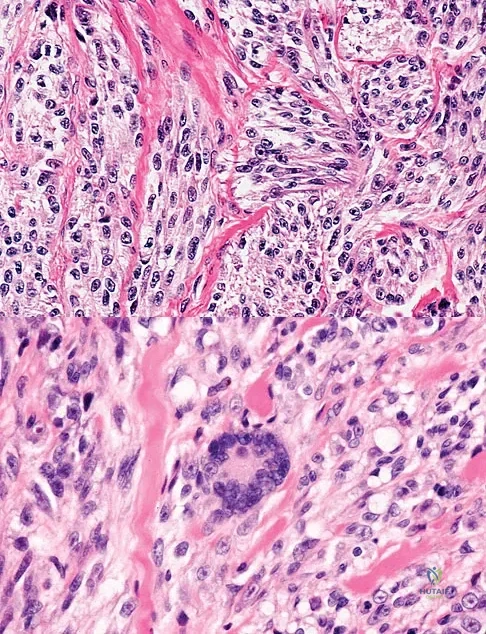

A 35-year-old man reports the development of a painful 2-cm nodule on his dorsal wrist over the past 3 years. A surgeon excised the lesion with a presumptive diagnosis of a ganglion cyst. Histology sections from the excision are shown in Figures 11a and 11b. What is the most likely diagnosis?

Explanation

A 16-year-old girl has had hip pain for 1 year. Approximately 2 months ago she noted the development of a hard mass in the right buttock that has steadily increased in size. She now reports severe pain in the right buttock, with radiation down the leg and numbness involving the right foot and toes. A radiograph is shown in Figure 70a and an axial postcontrast T1-weighted MRI scan is shown in Figure 70b. A biopsy specimen is shown in Figure 70c. The chest CT shows multiple lung metastases. Treatment of this lesion should consist of

Explanation